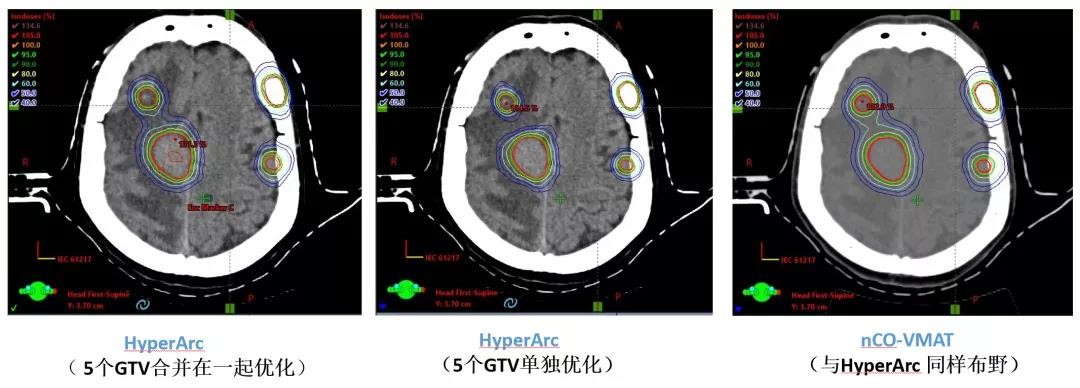

肺癌脑多发转移,5个靶点,最大直径3cm,48Gy/12F,

CI:1.14、5mm外跌落到50%处方剂量

HyperArc剂量跌落明显优于传统非共面VMAT治疗,

而且对于多发脑转移,各靶点单独优化,效果更好